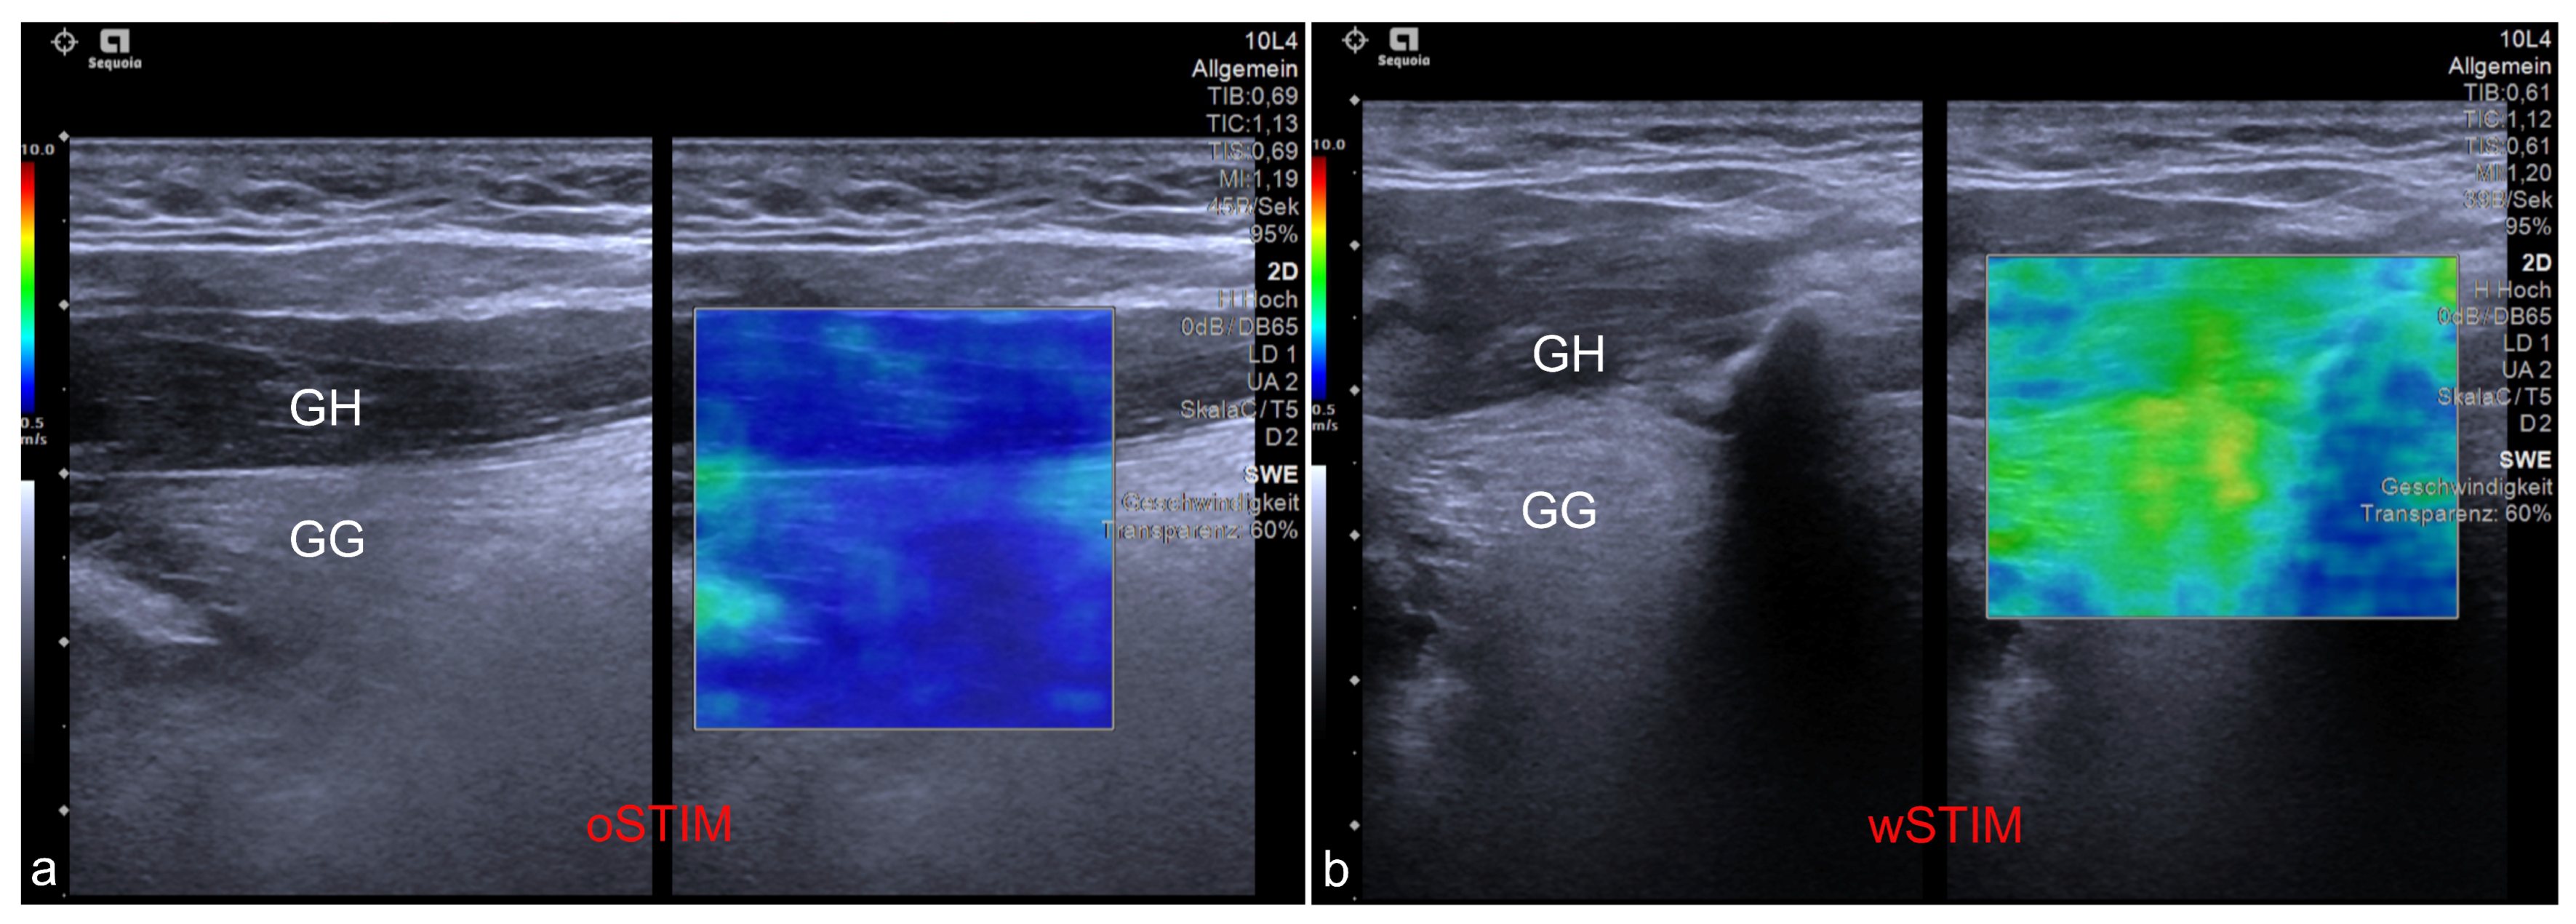

- Arens, P.; Fischer, T.; Dommerich, S.; Olze, H.; Lerchbaumer, M.H. Ultrasound Shear Wave Elastography of the Tongue during Selective Hypoglossal Nerve Stimulation in Patients with Obstructive Sleep Apnea Syndrome. Ultrasound Med. Biol. 2021, 47, 2869–2879. [Google Scholar] [CrossRef]